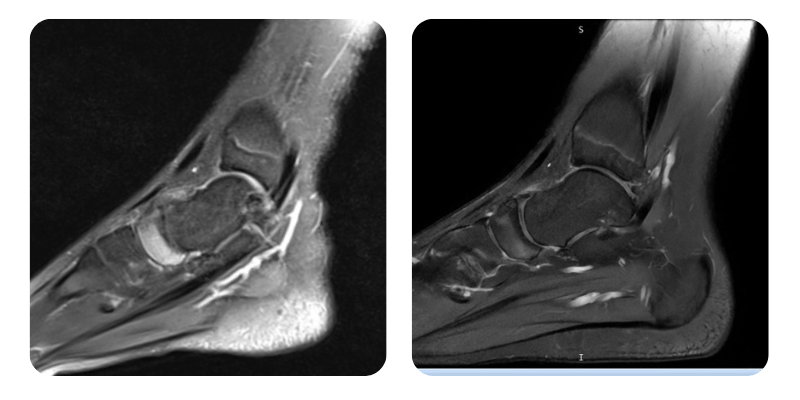

Vorher

Nachher

Anamnese: Der Patient stellt sich mit einer aseptischen Osteonekrose des linken Os naviculare vor. Vor 7 Monaten erlitt er eine Verstauchung, die vorübergehend abklang. Seit einem Monat sind die Schmerzen im Fuß erneut aufgetreten. Die Diagnose wurde mittels MRT gestellt. Schmerzintensität 6–7/10, insbesondere morgens. Keine chronische Medikation, keine relevanten Vorerkrankungen.

Ergebnisse: MRT des Fußes.

Verlauf: Bei der Nachkontrolle berichtet der Patient, dass die Schmerzen nahezu vollständig abgeklungen sind – etwa 1/10 im Vergleich zu 6–7/10 initial. Die Mobilität hat sich verbessert. Das Kontroll-MRT zeigt eine Reduktion des Ödems um ca. 70%.